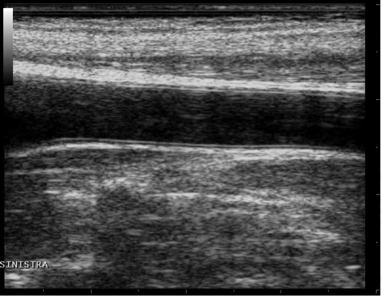

The artery should be viewed in longitudinal section and should be as horizontal as possible to the image. For Carotid Studio we recommend an image depth of 3-4 cm.

images/download/attachments/381258618/en_Ultrasound_Carotid-version-1-modificationdate-1759328517231-api-v2.png

Example of carotid artery image